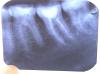

Hope Опубликовано 17 сентября, 2006 Поделиться Опубликовано 17 сентября, 2006 Да ,всё очень подробно,кроме одного-чем пломбировали каналы? Влад,помнишь горе пациента с форфенаном в зубах? Коллеги, а вам не кажется, что в дистальном канале фрагмент инструмента? Ссылка на комментарий

Doc Опубликовано 17 сентября, 2006 Поделиться Опубликовано 17 сентября, 2006 Коллеги, а вам не кажется, что в дистальном канале фрагмент инструмента? Снимок не сильно качественный, потому в дистальном ничего сказать не могу. Может у меня в глазах рябит, но я вижу на медиальном корне восьмерки ровно посередине стоящий поперек фрагмент каналонаполнителя. Понимаю, что это скорее всего артефакт, но так похож!!! Ссылка на комментарий